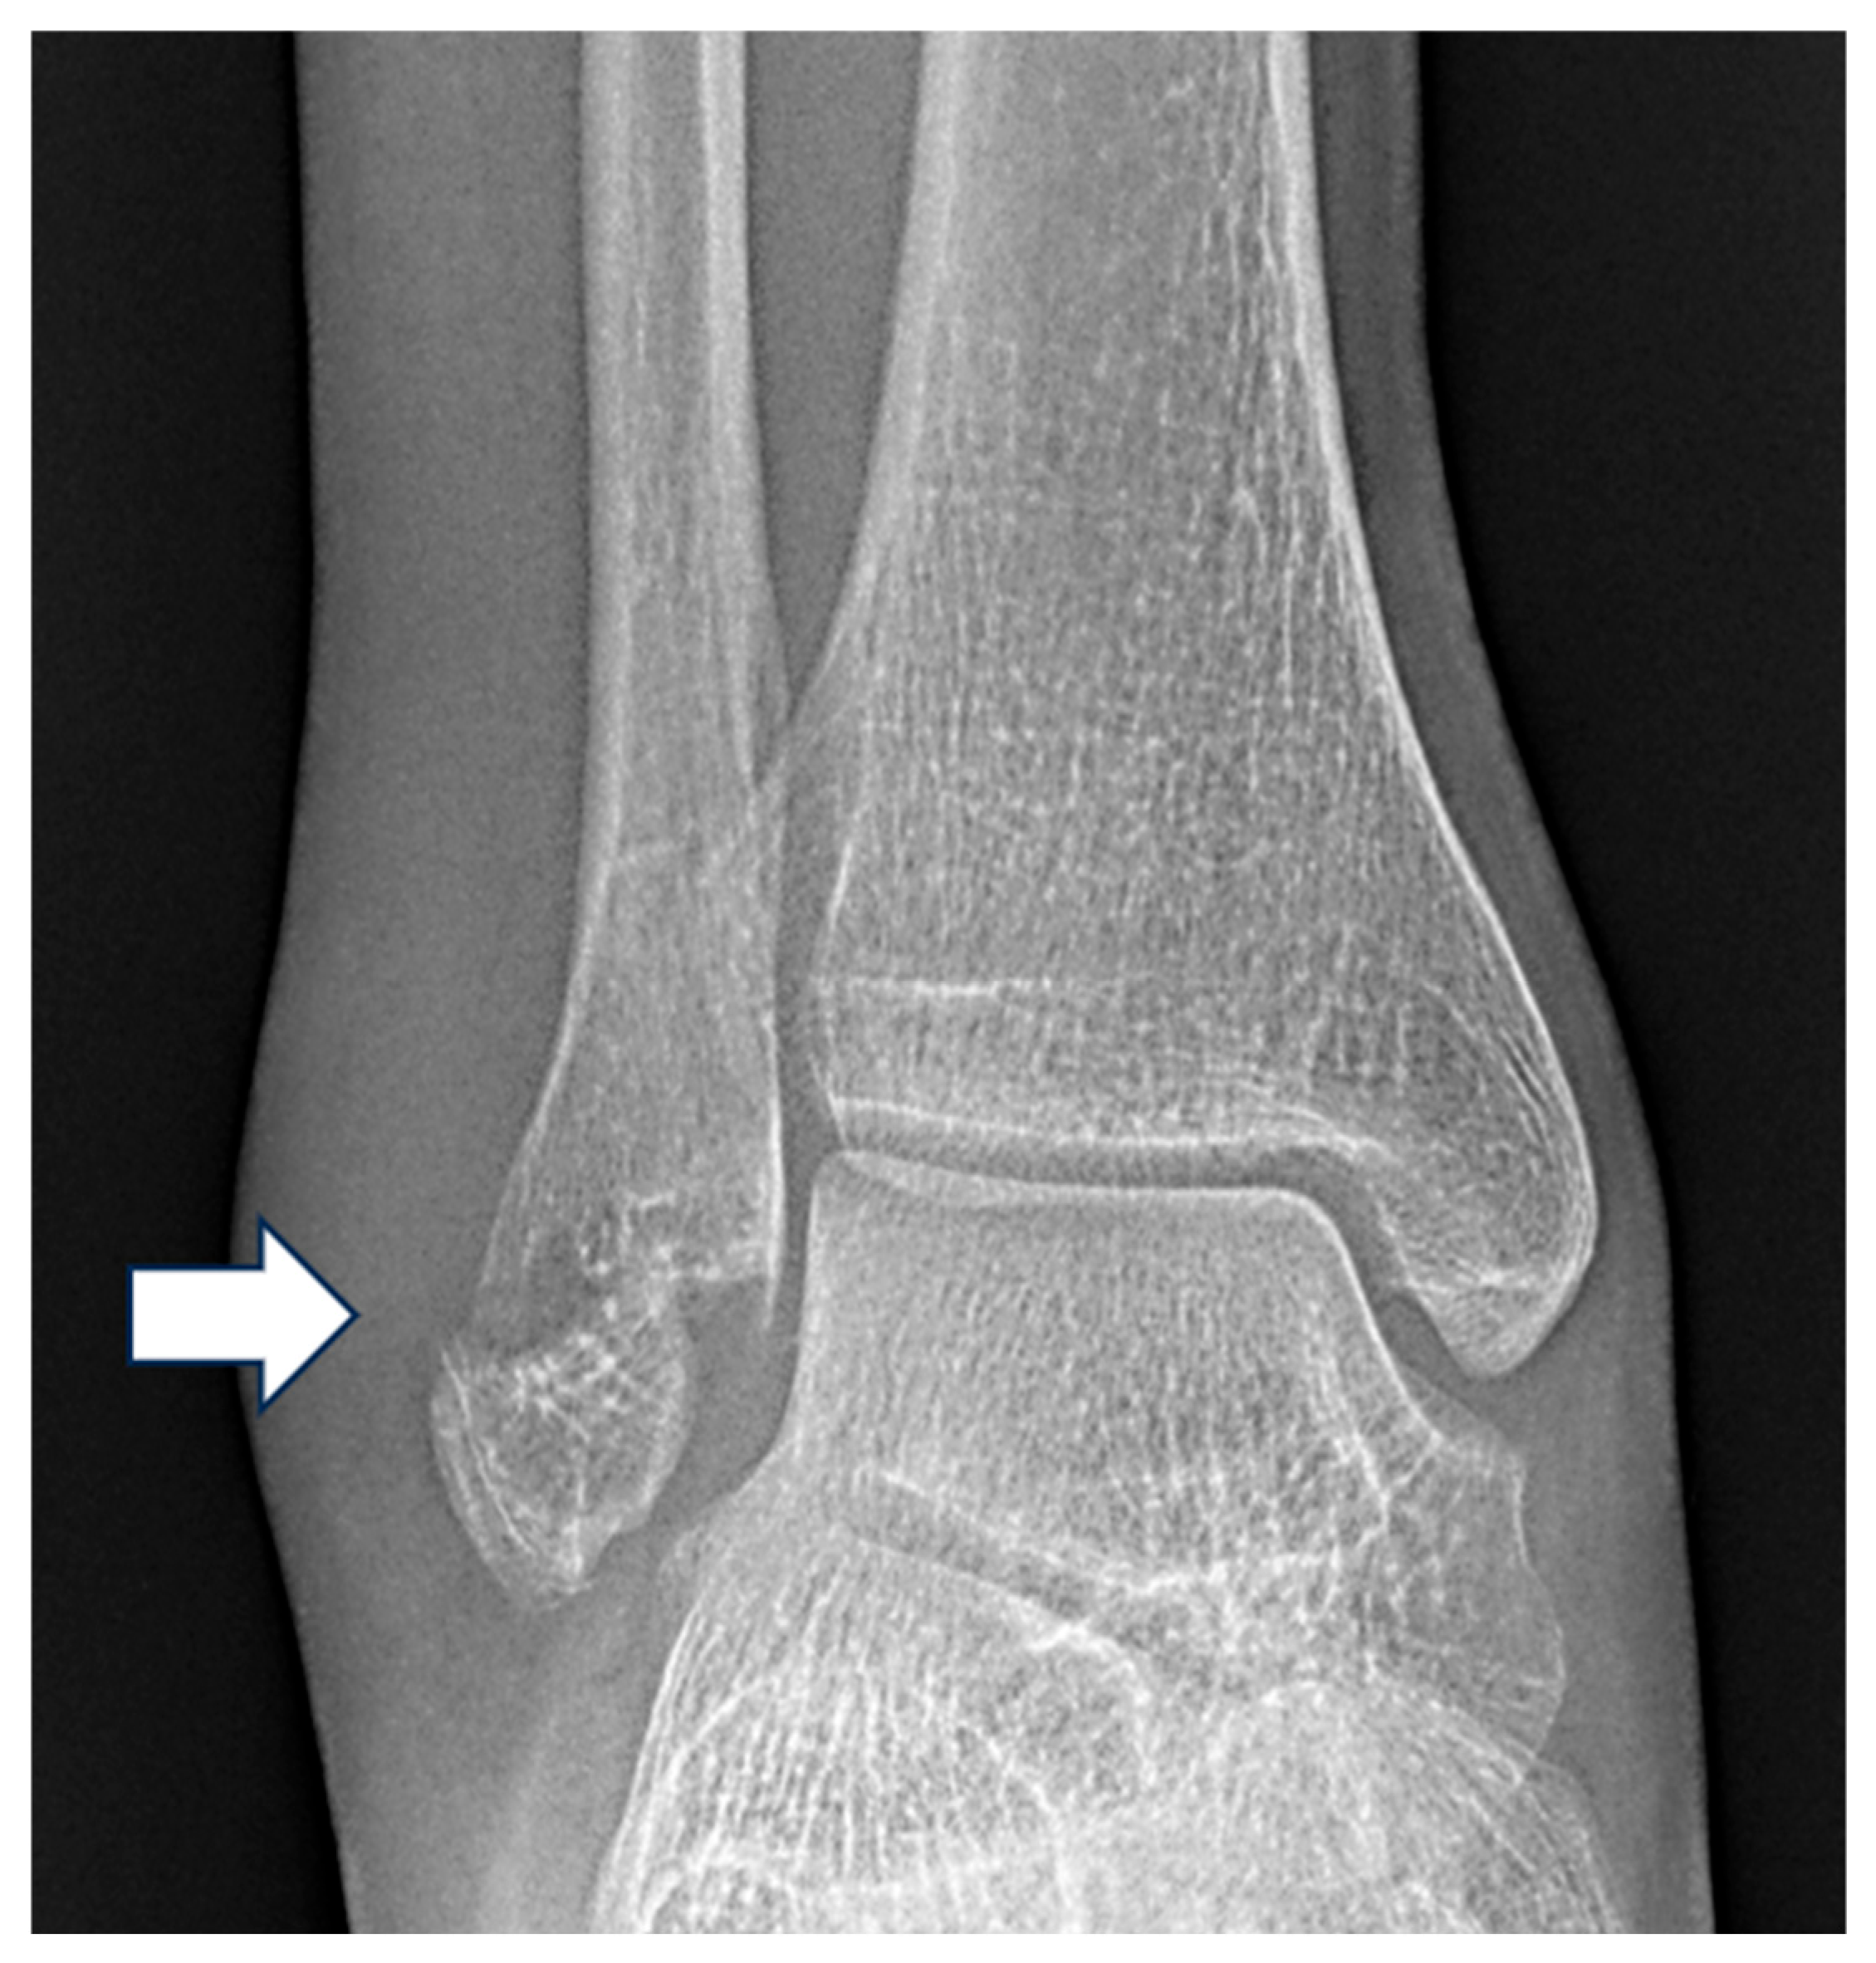

| Pattern (n) | Measurement | Mean ± Standard Deviation (mm) |

|---|---|---|

| Weber A (127) | Medial Clear Space | 3.3 ± 1.1 |

| Lateral Clear Space | 4.2 ± 1.4 | |

| Superior Clear Space | 3.4 ± 0.7 | |

| Weber B (216) | Medial Clear Space | 4.4 ± 2.4 |

| Lateral Clear Space | 4.4. ± 1.5 | |

| Superior Clear Space | 3.6 ± 0.7 | |

| Weber C (130) | Medial Clear Space | 5.7 ± 3.6 |

| Lateral Clear Space | 5.8 ± 2.9 | |

| Superior Clear Space | 3.7 ± 0.9 |